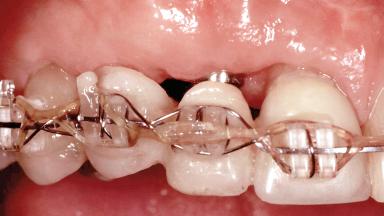

Replacement of Teeth 12 and 13 with Tissue-Level Implants

Prosthesis Type FDP

Loading Protocol Conventional or early

Retention Cemented, with prosthesis margin < 3mm submucosal Cemented, with prosthesis margin < 3mm submucosal

Interim Prosthesis during Healing Fixed Fixed